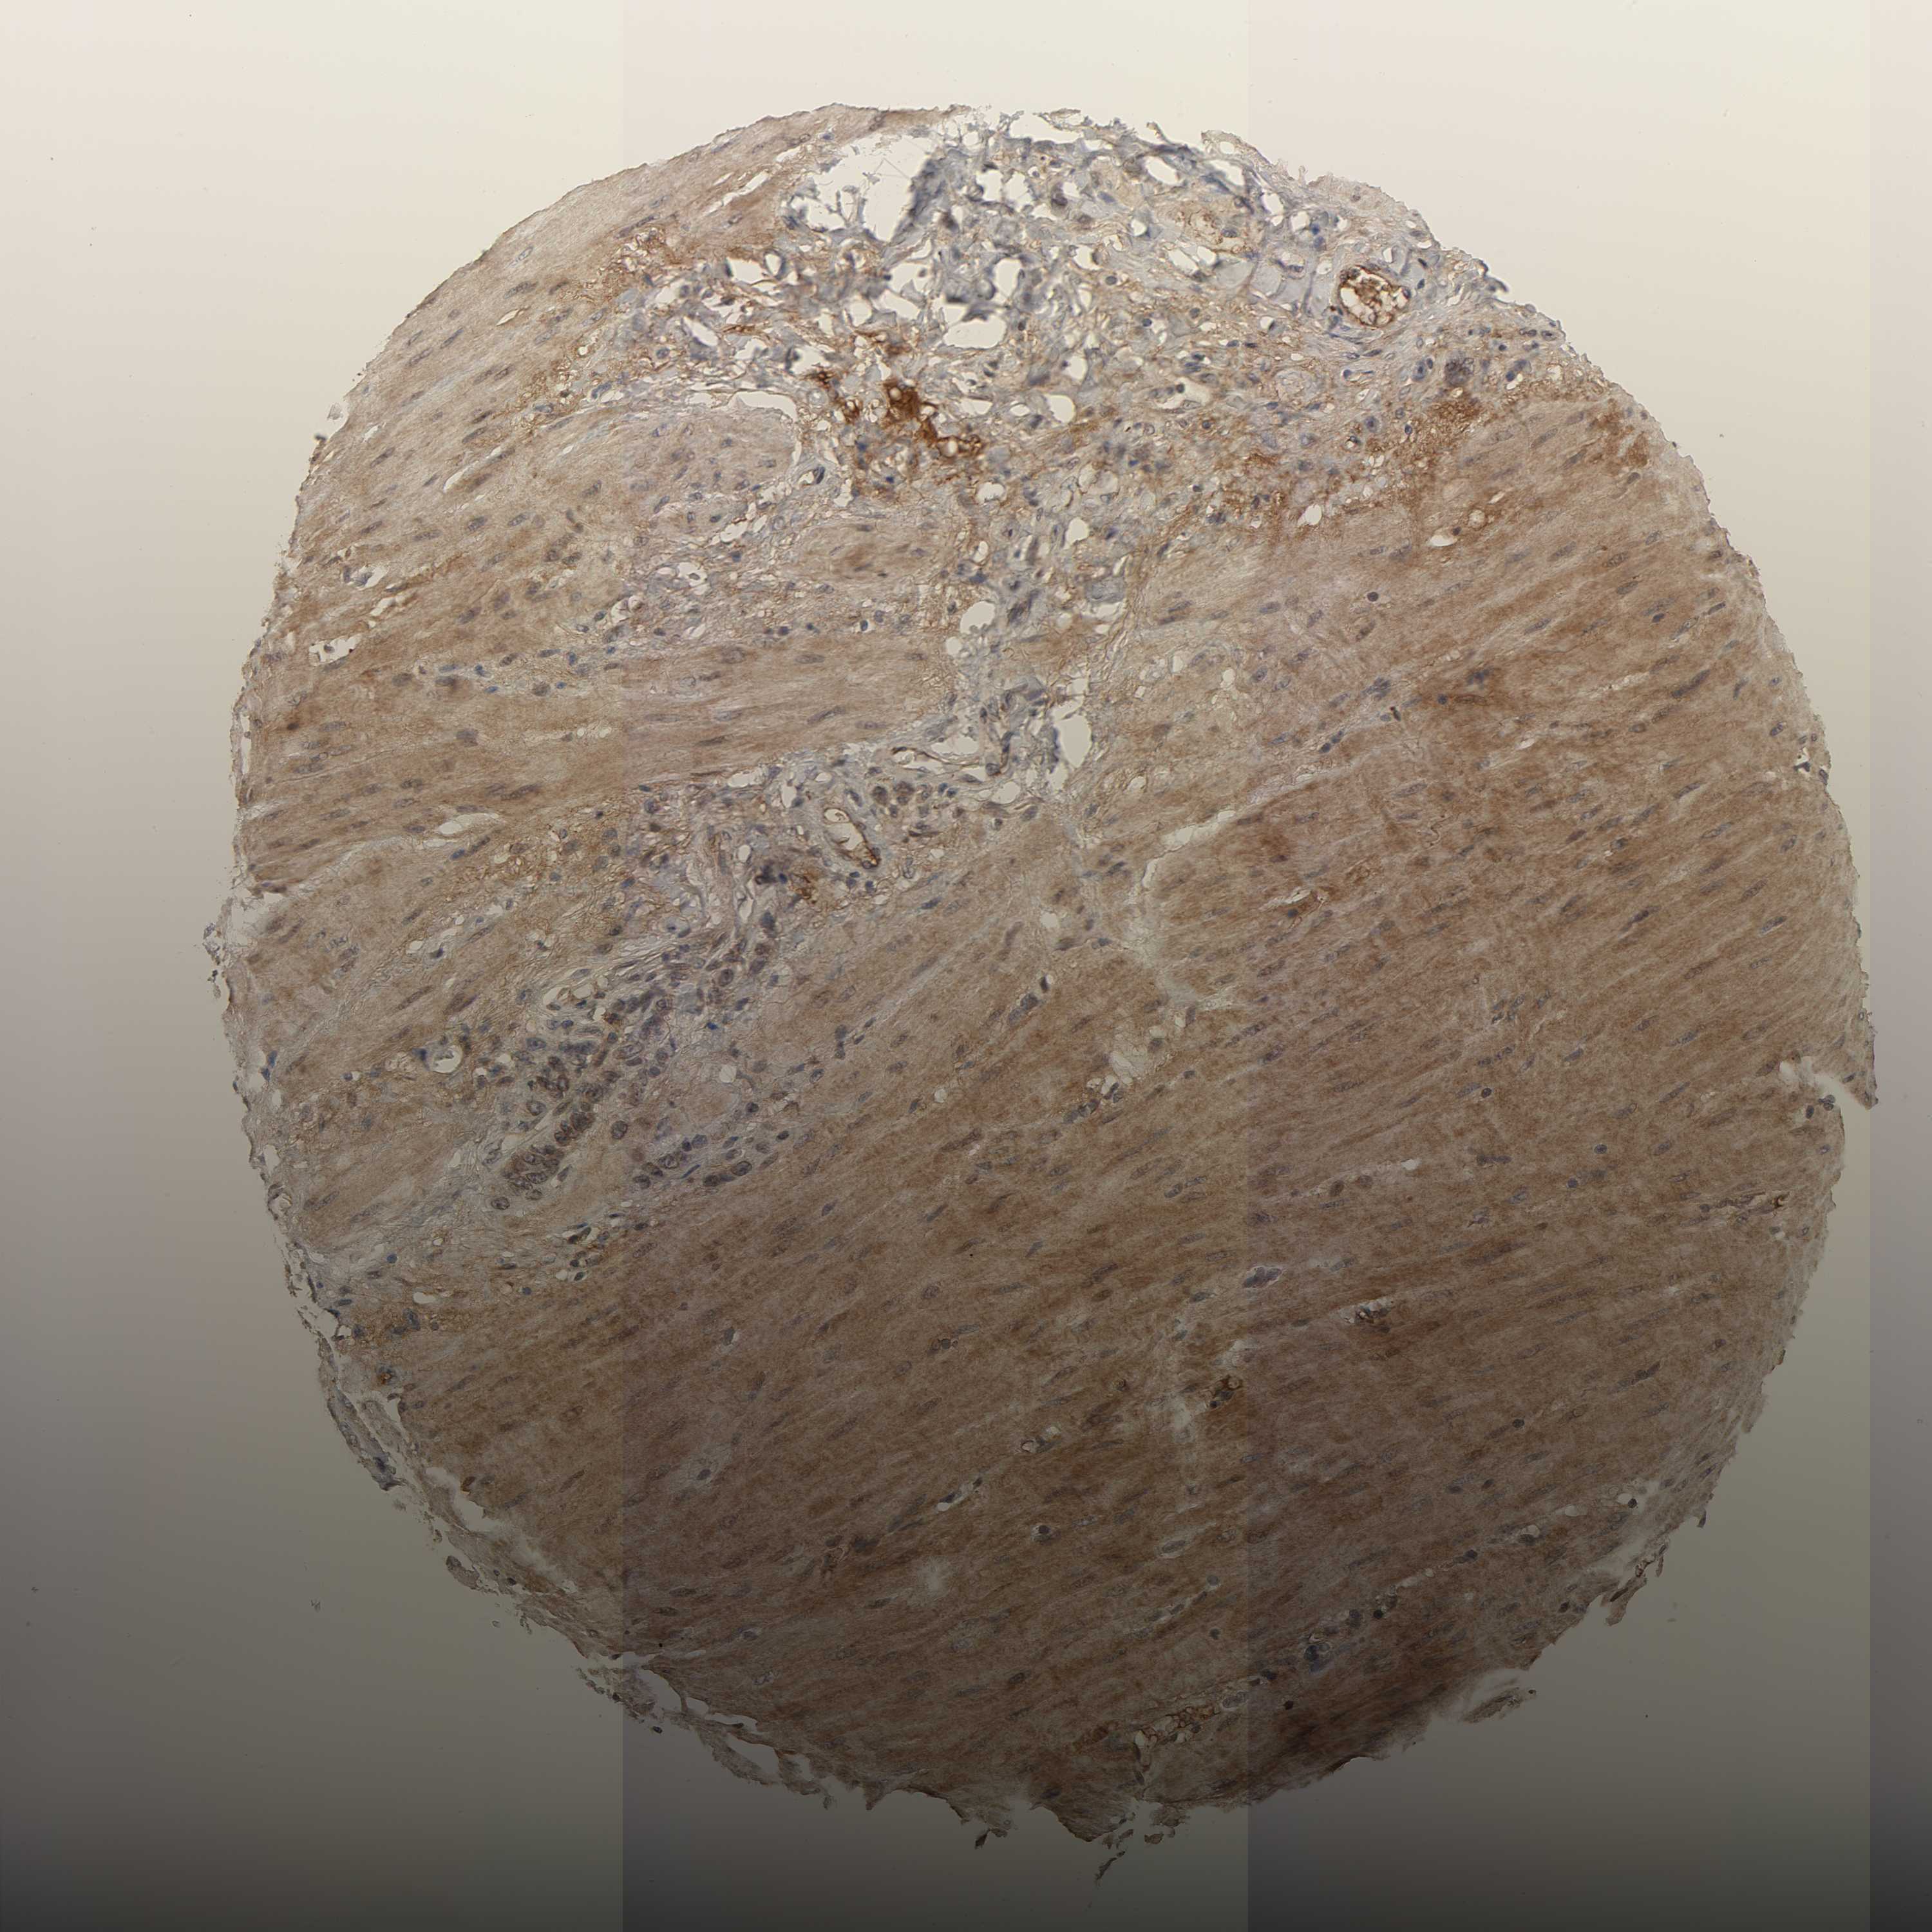

STOMACH CANCER - Protein expressioni

A mouse-over function shows sample information and annotation data. Click on an image to view it in a full screen mode. Samples can be filtered based on level of antibody staining by selecting one or several of the following categories: high, medium, low and not detected. The assay and annotation is described here.

Note that samples used for immunohistochemistry by the Human Protein Atlas do not correspond to samples in the TCGA dataset.

Antibody stainingi

Antibody staining in the annotated cell types in the current human tissue is reported as not detected, low, medium, or high, based on conventional immunohistochemistry profiling in selected tissues. This score is based on the combination of the staining intensity and fraction of stained cells.

Each image is clickable and will lead to virtual microscopy that enables deeper exploration of all samples and also displays staining intensity scores, fraction scores and subcellular localization as well as patient and tissue information for each sample.

Antibody HPA004732

Staining

High

Medium

Low

Not detected

Intensity

Strong

Moderate

Weak

Negative

Quantity

>75%

75%-25%

<25%

None

Location

Nuclear

Cytoplasmic/membranous

Cytoplasmic/membranous,nuclear

Adenocarcinoma, NOS

Adenocarcinoma, High grade